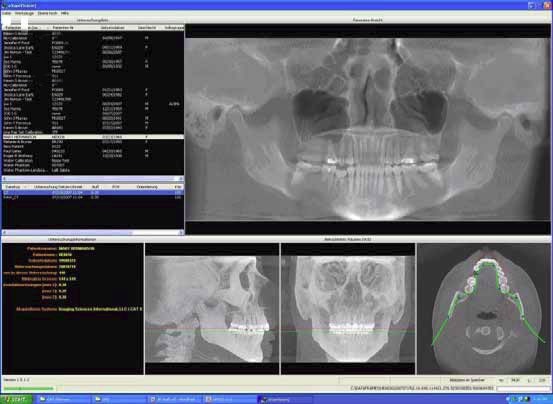

Neuste 3D-Röntgentechnik

mit dem digitalen Volumentomograph („Kopf-CT“)

Viele Krankheitsbilder erfordern

eine genaue Röntgendiagnostik. Hier bietet die neuartige

digitale Volumentomographie (DVT) bisher unvorstellbare Möglichkeiten:

In nur 10 Sekunden werden bis zu 600 Einzelbilder von Kopf,

Zähnen und Kiefergelenken aufgenommen, die zu einem dreidimensionalen

Bild verbunden werden.

Dies bietet phantastische 3D-Einblicke in versteckte Regionen

und ermöglicht Untersuchungen aus anderen Blickwinkeln.

So kann z.B. am Computer jeder Eingriff geplant und die 3D-Ansicht

des Kiefers in jeder beliebigen Ebene rekonstruiert werden.